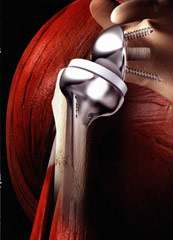

Eine Schulter-Endoprothese, auch Schulterprothese genannt, ist dem natürlichen menschlichen Schultergelenk nachempfunden. Es kann sowohl der Oberarmkopf als auch die Schulterpfanne ersetzt werden – oder beides.

Die Wahl des Implantats hängt von der Funktion der Muskulatur ab, die das Schultergelenk umgibt. Denn diese Muskeln, die sogenannte Rotatorenmanschette, führen und stabilisieren das Schultergelenk. Ist die Gelenkfläche durch Arthrose oder einen Mehrfragmentbruch zerstört, die Rotatorenmanschette jedoch intakt, brauchen wir nur die Oberfläche des Oberarmkopfes zu ersetzen. In speziellen Fällen ist die Überkleidung der Gelenkfläche der Schultergelenkspfanne (Glenoid) mit Polyethylen erforderlich.

Inverse Schulterprothese (auch Deltaprothese)

Bei der inversen (umgekehrten) Schulterprothese werden die Gelenkpartner des Schultergelenks vertauscht: An der Stelle, an der beim Menschen der Oberarmkopf liegt, wird eine Gelenkpfanne eingebracht und dort, wo sich bei normaler Anatomie die Gelenkpfanne befindet, wird eine dem Oberarmkopf ähnliche Halbkugel befestigt. Die inverse Prothese eignet sich deswegen für Patienten mit zerstörter Rotatorenmanschette, weil sie das Drehzentrum der Schulter nach unten und innen verlagert. So ist man für die Funktion der Prothese nur auf einen Muskel angewiesen – und zwar auf den Deltamuskel. Die Schulter kann dann anschließend wieder normal und schmerzfrei bewegt werden.